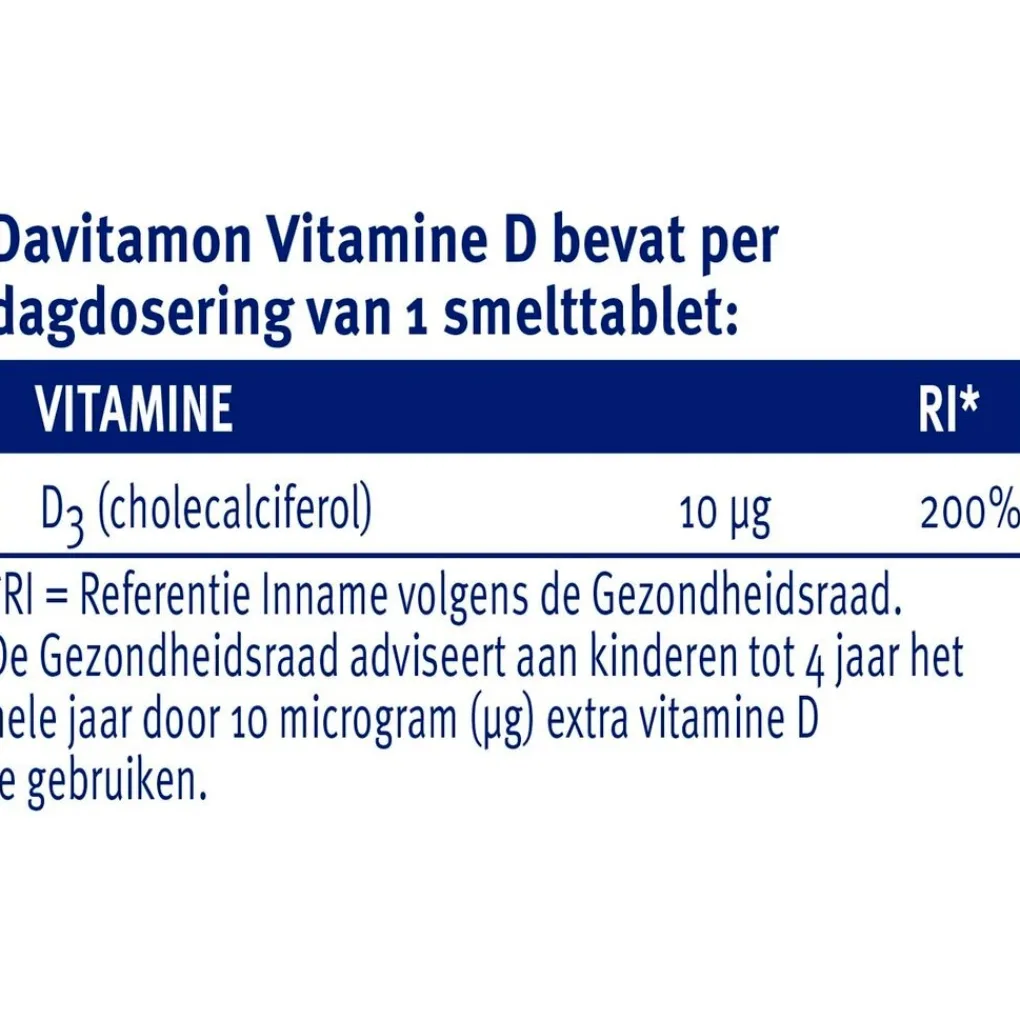

Samenstelling

Samenstelling:# Davitamon Vitamine D bevat per dagdosering van 1 smelttablet:#Vitamine;

; ;RI*# D3 (cholecalciferol);10;µg;200%# *RI=Referentie Inname volgens de Gezondheidsraad.